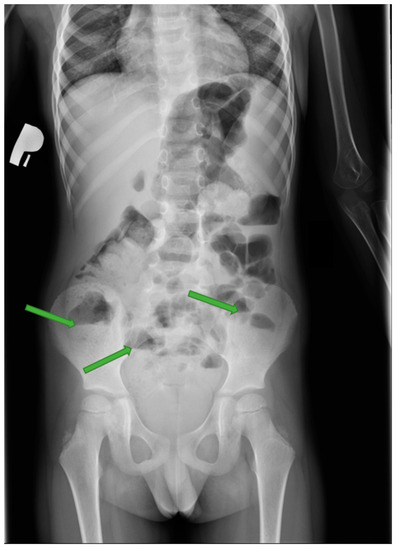

4. Case Presentation

5.3. Imaging